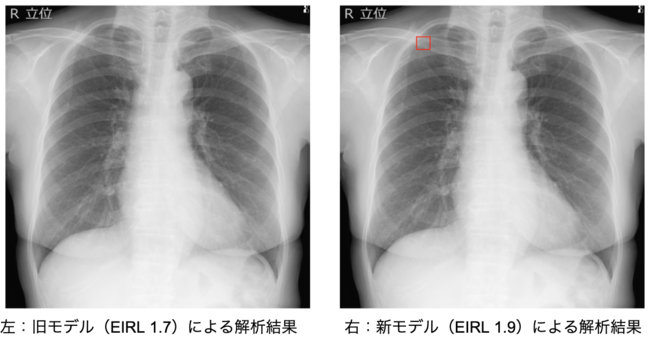

肺結節候補域の検出感度が向上

新モデルのソフトウェア単体性能試験において,旧モデルと比較した場合,12.2%以上の検出感度の向上が認められた。*2

<旧モデルでは検出できなかったが新モデルで検出できた例>

<旧モデル (EIRL 1.7) > 感度 62.1%以上

<新モデル (EIRL 1.9) > 感度 74.3%以上